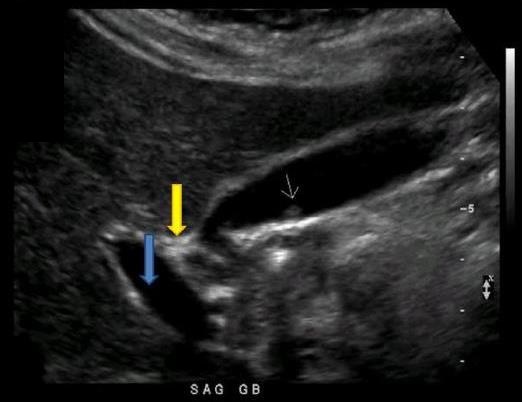

Which of the following statements is true regarding the image displayed?

The gallbladder has a normal variant called a Phrygian cap near the fundal area

What structure is indicated by the blue arrow?

Right portal vein

what liver vessels indicated by the yellow arrow?

Anterior right portal vein

What structure is indicated by the yellow arrow?

Main lobar fissure

Which portions of the gallbladder and/or Billary tree are involved in the formation of a Phrygian cap?

Body and Fundus